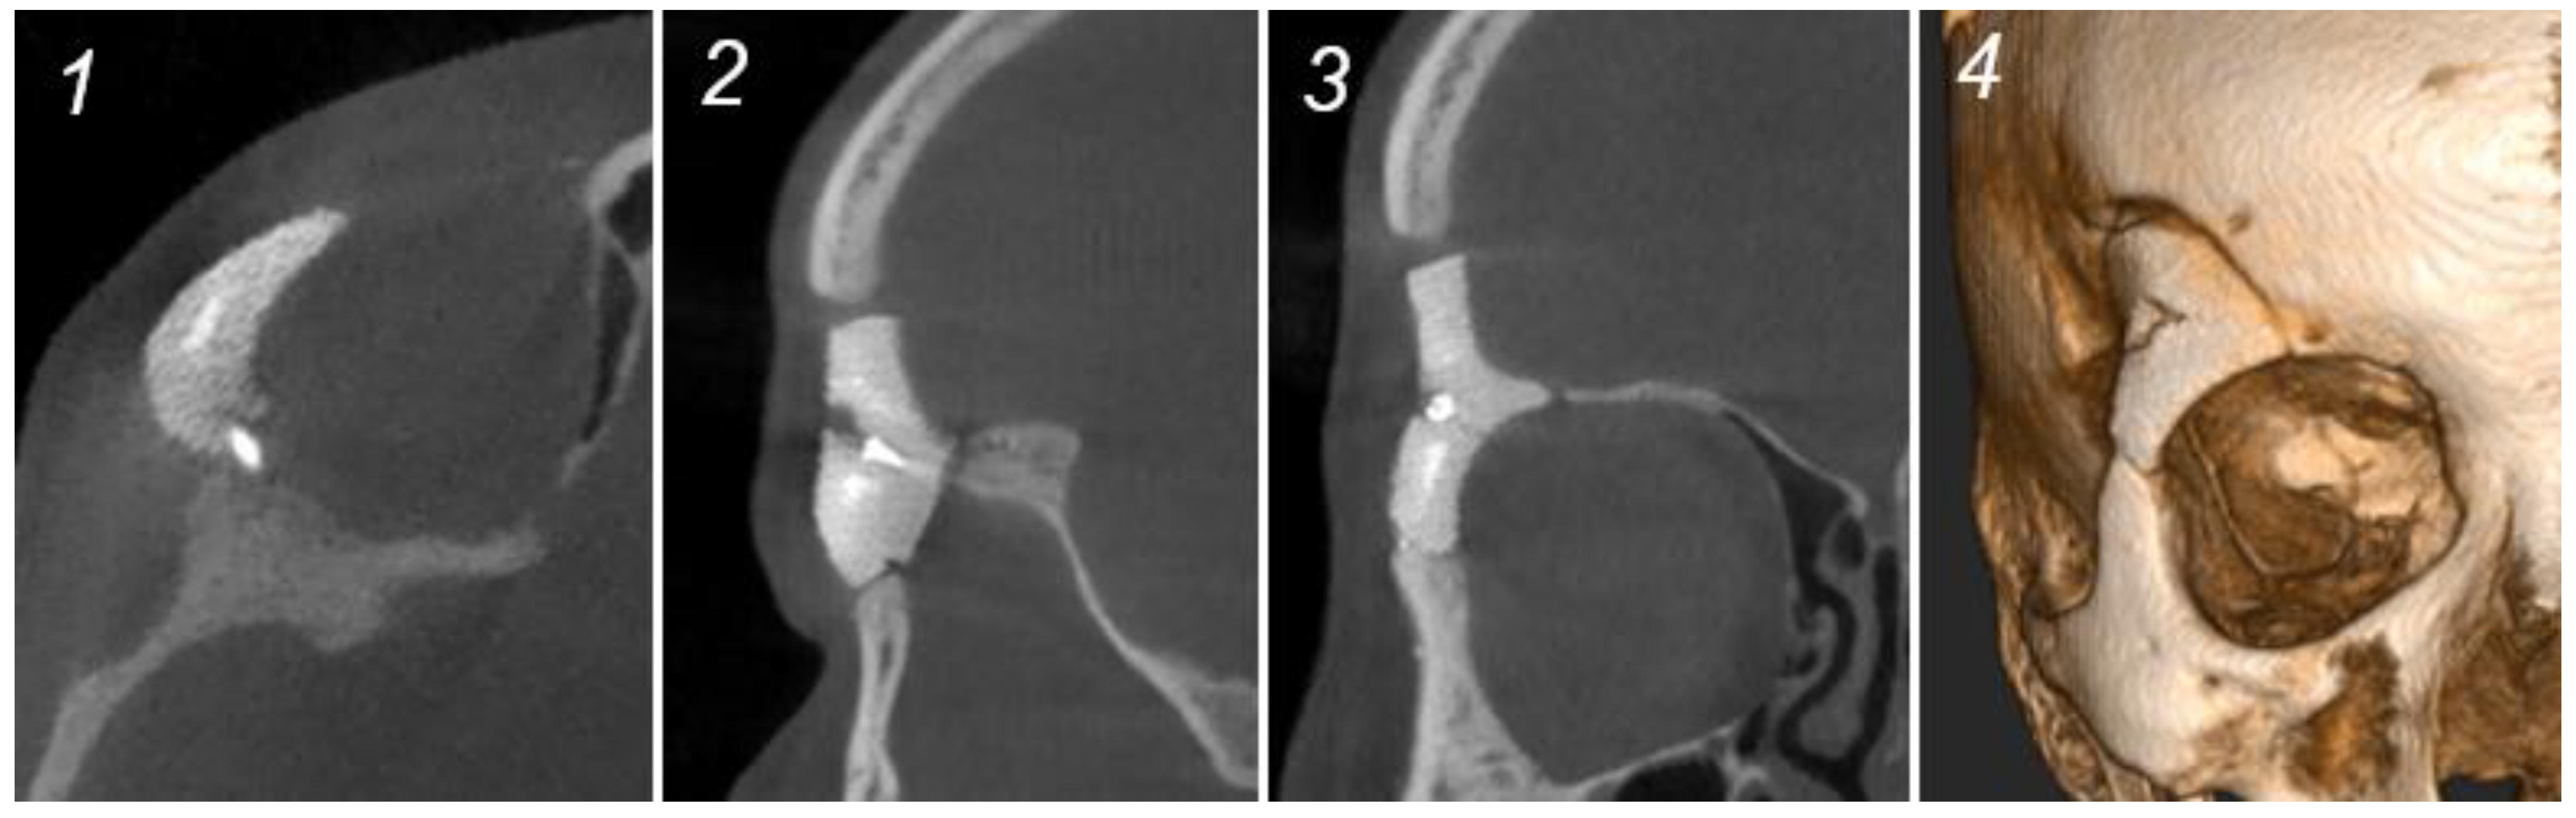

Figure 4.

Radiological (CBCT) and clinical situation after 6 months, case 1. (1): Axial plane. (2): Sagittal plane—signs of osteogenesis. (3): Frontal plane—signs of osteogenesis. (4): 3D CT image.

The first clinical case showed good ocular vision, normal ocular mobility, and satisfactory aesthetic results with maximal preservation of facial symmetry after one week, two months, and six months of clinical and radiological follow-up (Figure 4). Mild right-sided hypoesthesia of the first and second branches of the trigeminal nerve was reported after two months, which resolved spontaneously six months postoperatively. Good positioning and contouring of the PSI after six months were identified on cone-beam CT (CBCT) imaging (Figure 4).

HA bioceramic PSIs are biomimetic and eliminate the need for bone grafts [17]. They are osteoconductive and the gyroid macroporosities have the potential to guide osteoblasts and facilitate osteogenesis and fibrovascular ingrowth in vitro [18]. In vivo, osseointegration could not be objectively evaluated on CT images after six months postoperatively in the two cases (Figure 3). However, in the first clinical case, optimal bone contact and signs of osteogenesis were observed between the PSI and the bone. This indicates a beneficial healing, fibrovascular ingrowth, and mineralization around the implant. The HA bioceramic PSI proved beneficial because of its use as an inlay instead of an onlay in case 1. This led to an excellent aesthetic result in this important anatomical region (Figure 3). Case 2 showed similar radiological signs of osteogenesis (Figure 5). To be able to radiologically observe obvious signs of osseointegration, a longer follow-up time of twelve months is required [9,16].